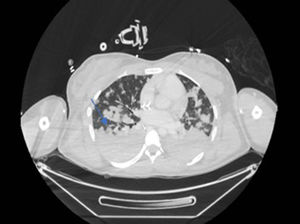

Evolución inicial desfavorable, con fiebre elevada, dolor abdominal y empeoramiento respiratorio progresivo que requirió iniciar oxigenoterapia nasal de alto flujo. En la radiografía de tórax al ingreso comienza a apreciarse infiltrado intersticial con consolidaciones basales. Iniciamos cobertura empírica con ceftriaxona, cloxacilina y doxiciclina, a la espera de resultados y de la evolución. A las pocas horas de ingreso, en situación de insuficiencia respiratoria franca, precisa intubación orotraqueal urgente con hipoxemia refractaria a maniobras de reclutamiento alveolar, así como inestabilidad hemodinámica progresiva en situación de shock vasopléjico refractario con noradrenalina, vasopresina y corticoides; acidosis metabólica con hiperlactacidemia y oliguria. En disfunción multiorgánica (Sequential Organ Failure Assessment score [SOFA12]), se amplía la cobertura empírica con linezolid y meropenem, además de doxiciclina, iniciando técnicas continuas de depuración extrarrenal (hemodiafiltración) con anticoagulación regional con citrato. Posteriormente nos informan desde Microbiología de aislamiento en sangre de Chromobacterium violaceum, decidiendo asociar levofloxacino tras revisar la literatura, dado el perfil de resistencia de este microorganismo.

De forma paulatina la paciente va estabilizándose tanto desde el punto de vista respiratorio como del hemodinámico, permitiendo trasladarla para realizar estudio de extensión con tomografía axial computarizada (TAC), en el que se aprecian múltiples abscesos pulmonares (fig. 1), dos abscesos hepáticos e infarto esplénico (fig. 2)1; cráneo sin hallazgos.